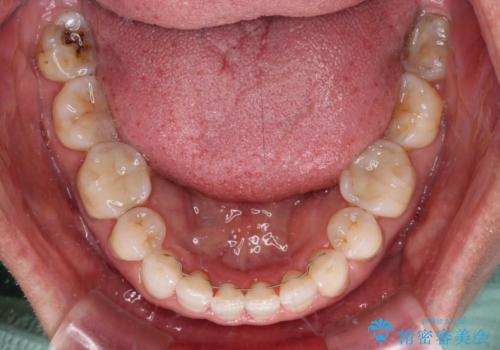

矯正治療の後戻り インビザライン・ライトでの再矯正

- 上下前歯を中心に、以前行った矯正治療の後戻りが気になるとのことで来院された患者様です。

後戻りは軽度であったため、インビザライン・ライトにて治療を行うこととしました。

矯正治療後は、再度後戻りすることを極力回避するために、下顎前歯の舌側を細いワイヤーを用いて保定することとしました。